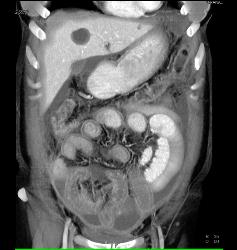

Linitis Plastica With Carcinomatosis